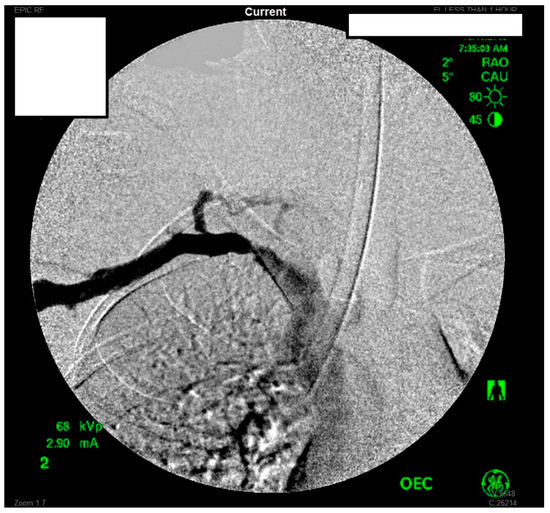

Figure 8.

Left subclavian arteriography in an ATOS patient in stress position demonstrating a totally occluded subclavian artery.